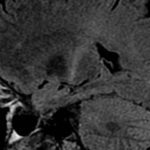

Immagine: Public Domain.

I ricercatori UVA hanno scoperto che il parassita, Toxoplasma gondii, è tenuto sotto controllo dai difensori del cervello chiamati microglia. Queste microglia rilasciano una molecola immunitaria unica, IL-1α, che recluta cellule immunitarie dal sangue per controllare il parassita nel cervello. Questo processo funziona così bene che pochissime persone sviluppano la toxoplasmosi sintomatica, la malattia causata dal parassita.

Comprendere il ruolo della microglia è essenziale perché sono normalmente le uniche cellule immunitarie all’interno del cervello. La nuova scoperta rivela come queste cellule reclutano aiuto quando necessario e potrebbe applicarsi a qualsiasi condizione cerebrale con una componente immunologica – tra cui lesioni cerebrali, malattie neurodegenerative, ictus, sclerosi multipla e altro ancora.

Un’area di interesse è la microglia e il suo ruolo nella difesa del cervello. Questa è stata una domanda difficile a cui rispondere perché le microglia sono strettamente correlate ad altre cellule immunitarie in altre parti del corpo. Fino a poco tempo fa, gli strumenti di laboratorio realizzati per colpire le microglia hanno preso di mira anche queste altre cellule, rendendo difficile la distinzione tra le due.